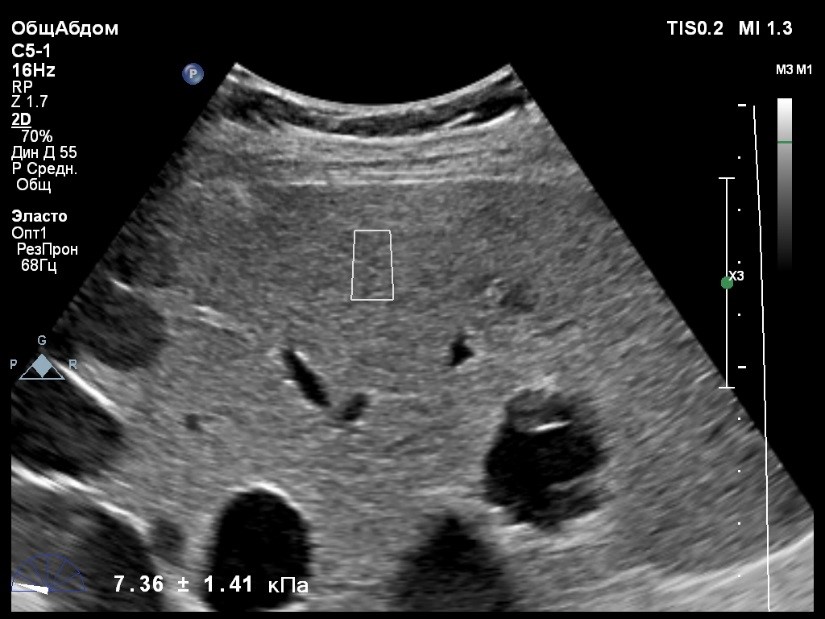

Пациент обратился к доктору с направлением на исследование степени жесткости печени в июне 2017 года. Из истории болезни, пациент страдает Гепатитом С с 2015 года. Лечение не получал. В апреле 2016 года, с помощью транзиентной эластографии была установлена медиана жесткости печени 5,8 kPA (4,4-7,7). На момент настоящего исследования, пациент не принимал пищу на протяжении 4 часов, АСТ, АЛТ не превышают патологических значений. Для оценки жесткости была выбрана технология компании Philips ElastPQ (точечная эластография) и прибор компании Philips Epiq 7 Исследование было проведено в соответствии с клиническими рекомендациями для ультразвуковых приборов компании Philips. В результате исследования были получены следующие результаты:

| 1 [4.94] kPa | 2 [7.09] kPa | 3 [7.13] kPa |

| 4 [4.74] kPa | 5 [5.17] kPa | 6 [7.78] kPa |

| 7 [6.19] kPa | 8 [7.63] kPa | 9 [4.64] kPa |

| 10 [6.18] kPa | 11 [4.49] kPa | 12 [4.54] kPa |

| 13 [6.08] kPa | | |

Стандартное Отклонение [1.17] kPa Медиана Жесткости [6.08] kPa Фактор Качества IQR/Med 9%

Зона интереса расположена на более чем на один сантиметр глубже капсулы, параллельно ходу луча, в середине изображения, в участке печени лишенном артефактов.

Капсула видна как белая линия перпендикулярная ходу ультразвукового луча, исследования производятся приблизительно в одном и том же сегменте печени.

Стандартное отклонение (0,96 kPA) не превышает 30 процентов от полученного значения (4,54 kPA).

Зона интереса расположена вне крупных сосудов.

Для интерпретации полученных клинических данных были использованы Рекомендации по проведению эластографии сдвиговой волной для оценки жесткости печени при использовании ультразвуковых аппаратов компании Филипс с примером протокола. Анамнез основного заболевания пациента достаточно короткий и показатели жесткости печени, полученные в 2016 свидетельствуют об отсутствии значимых фиброзных изменений. Однако, в течении всего времени пациент не получал специфического лечения. Данный факт является показанием для динамического наблюдения и оценки жесткости печени. Подготовка пациента соответствовала проводимому исследованию. Представленные слайды проведенного исследования свидетельствуют о правильном техническом исполнении проб, что позволяет заключиться о достоверности полученных измерений. Таким образом, учитывая полученную медиану жесткости на уровне 6.08 кРа (4.49 – 7.78 kPa) и уровень стандартных отклонений не превышающих 30%, полагаю, что уровень степени фиброза соответствует стадии F 0-1. Заведующий отделением УЗД МЦ «Асклепий», Глушенко Д. Е.